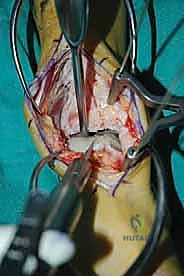

ثالثاً: الحل الجذري - إعادة بناء الطعم الخيفي الهيكلي

بالنسبة للمرضى الذين يعانون من آلام مزمنة، وتظهر صورهم آفة كبيرة الحجم، عميقة، تحتوي على تكيسات ضخمة، أو تشمل حواف التالوس (الكتف)، تصبح إعادة بناء الطعم الخيفي الهيكلي هي الحل الأمثل والذهبي.

الغوص العميق في جراحة الطعم الخيفي الهيكلي (Structural Allograft Reconstruction)

يهدف هذا الإجراء العبقري إلى استبدال الغضروف والعظم التالفين والميتين بنسيج سليم تماماً مأخوذ من متبرع متوفى (طعم خيفي - Allograft). هذا الطعم يتم تعقيمه وحفظه في بنوك الأنسجة العالمية وفقاً لأعلى المعايير الطبية الصارمة لضمان خلوه من أي أمراض معدية والحفاظ على حيوية الخلايا الغضروفية.

- الترميم التشريحي الحقيقي: يسمح باستعادة الشكل الهندسي الدقيق لعظم الكاحل، بما في ذلك المنحنيات المعقدة لكتف التالوس.

- توفير غضروف طبيعي (Hyaline Cartilage): الغضروف المزروع هو غضروف زجاجي طبيعي،